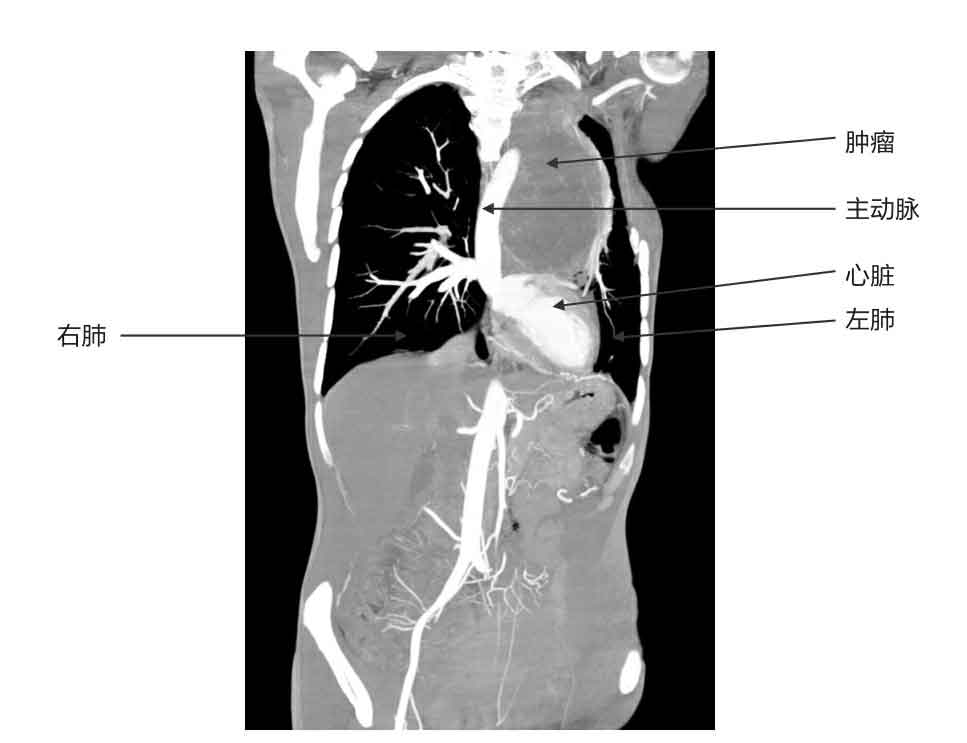

这位患者胸腔里的肿瘤太大了,它向后侵袭了八节脊椎,向前压迫了患者的气管、肺、肺动脉、肺静脉、心包。更可怕的是,肿瘤组织把主动脉包裹住了。

患者的影像学资料

巨大的肿瘤

他一边说话一边打开了电脑,找出患者的影像学资料。他对着电脑上的CT、核磁共振图像,给我一点点地讲。

“你看,要想把肿瘤切下来,先要从主动脉上把包着的肿瘤组织剥下来,还要从心脏、肺的表面把肿瘤分开。如果这一步能顺利完成,接下来就要完整地切掉八节被肿瘤组织侵犯的脊椎。切掉这么多脊椎,病人以后还怎么站啊?所以还要给他换上一大段3D打印的人工椎体。肿瘤这么大,周围组织全侵犯了,为了切干净,切掉肿瘤的同时还要切除肿瘤周围大量的肌肉、肋骨、软组织,这些缺损的组织怎么补?手术太难了!